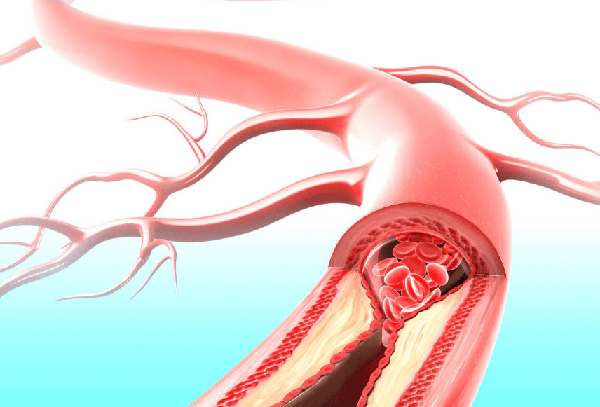

1、我们该如何维持我们的体格?重视血管的保健